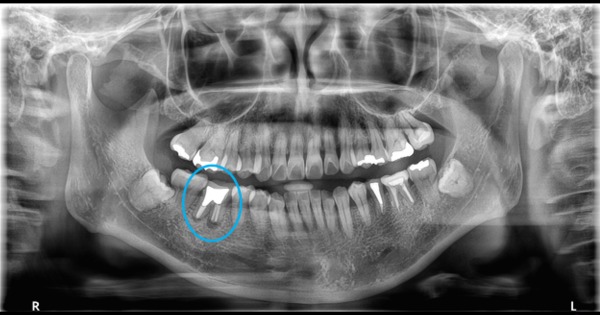

【症例】右下6臼歯部抜歯即時インプラント埋入

症例

インプラント治療